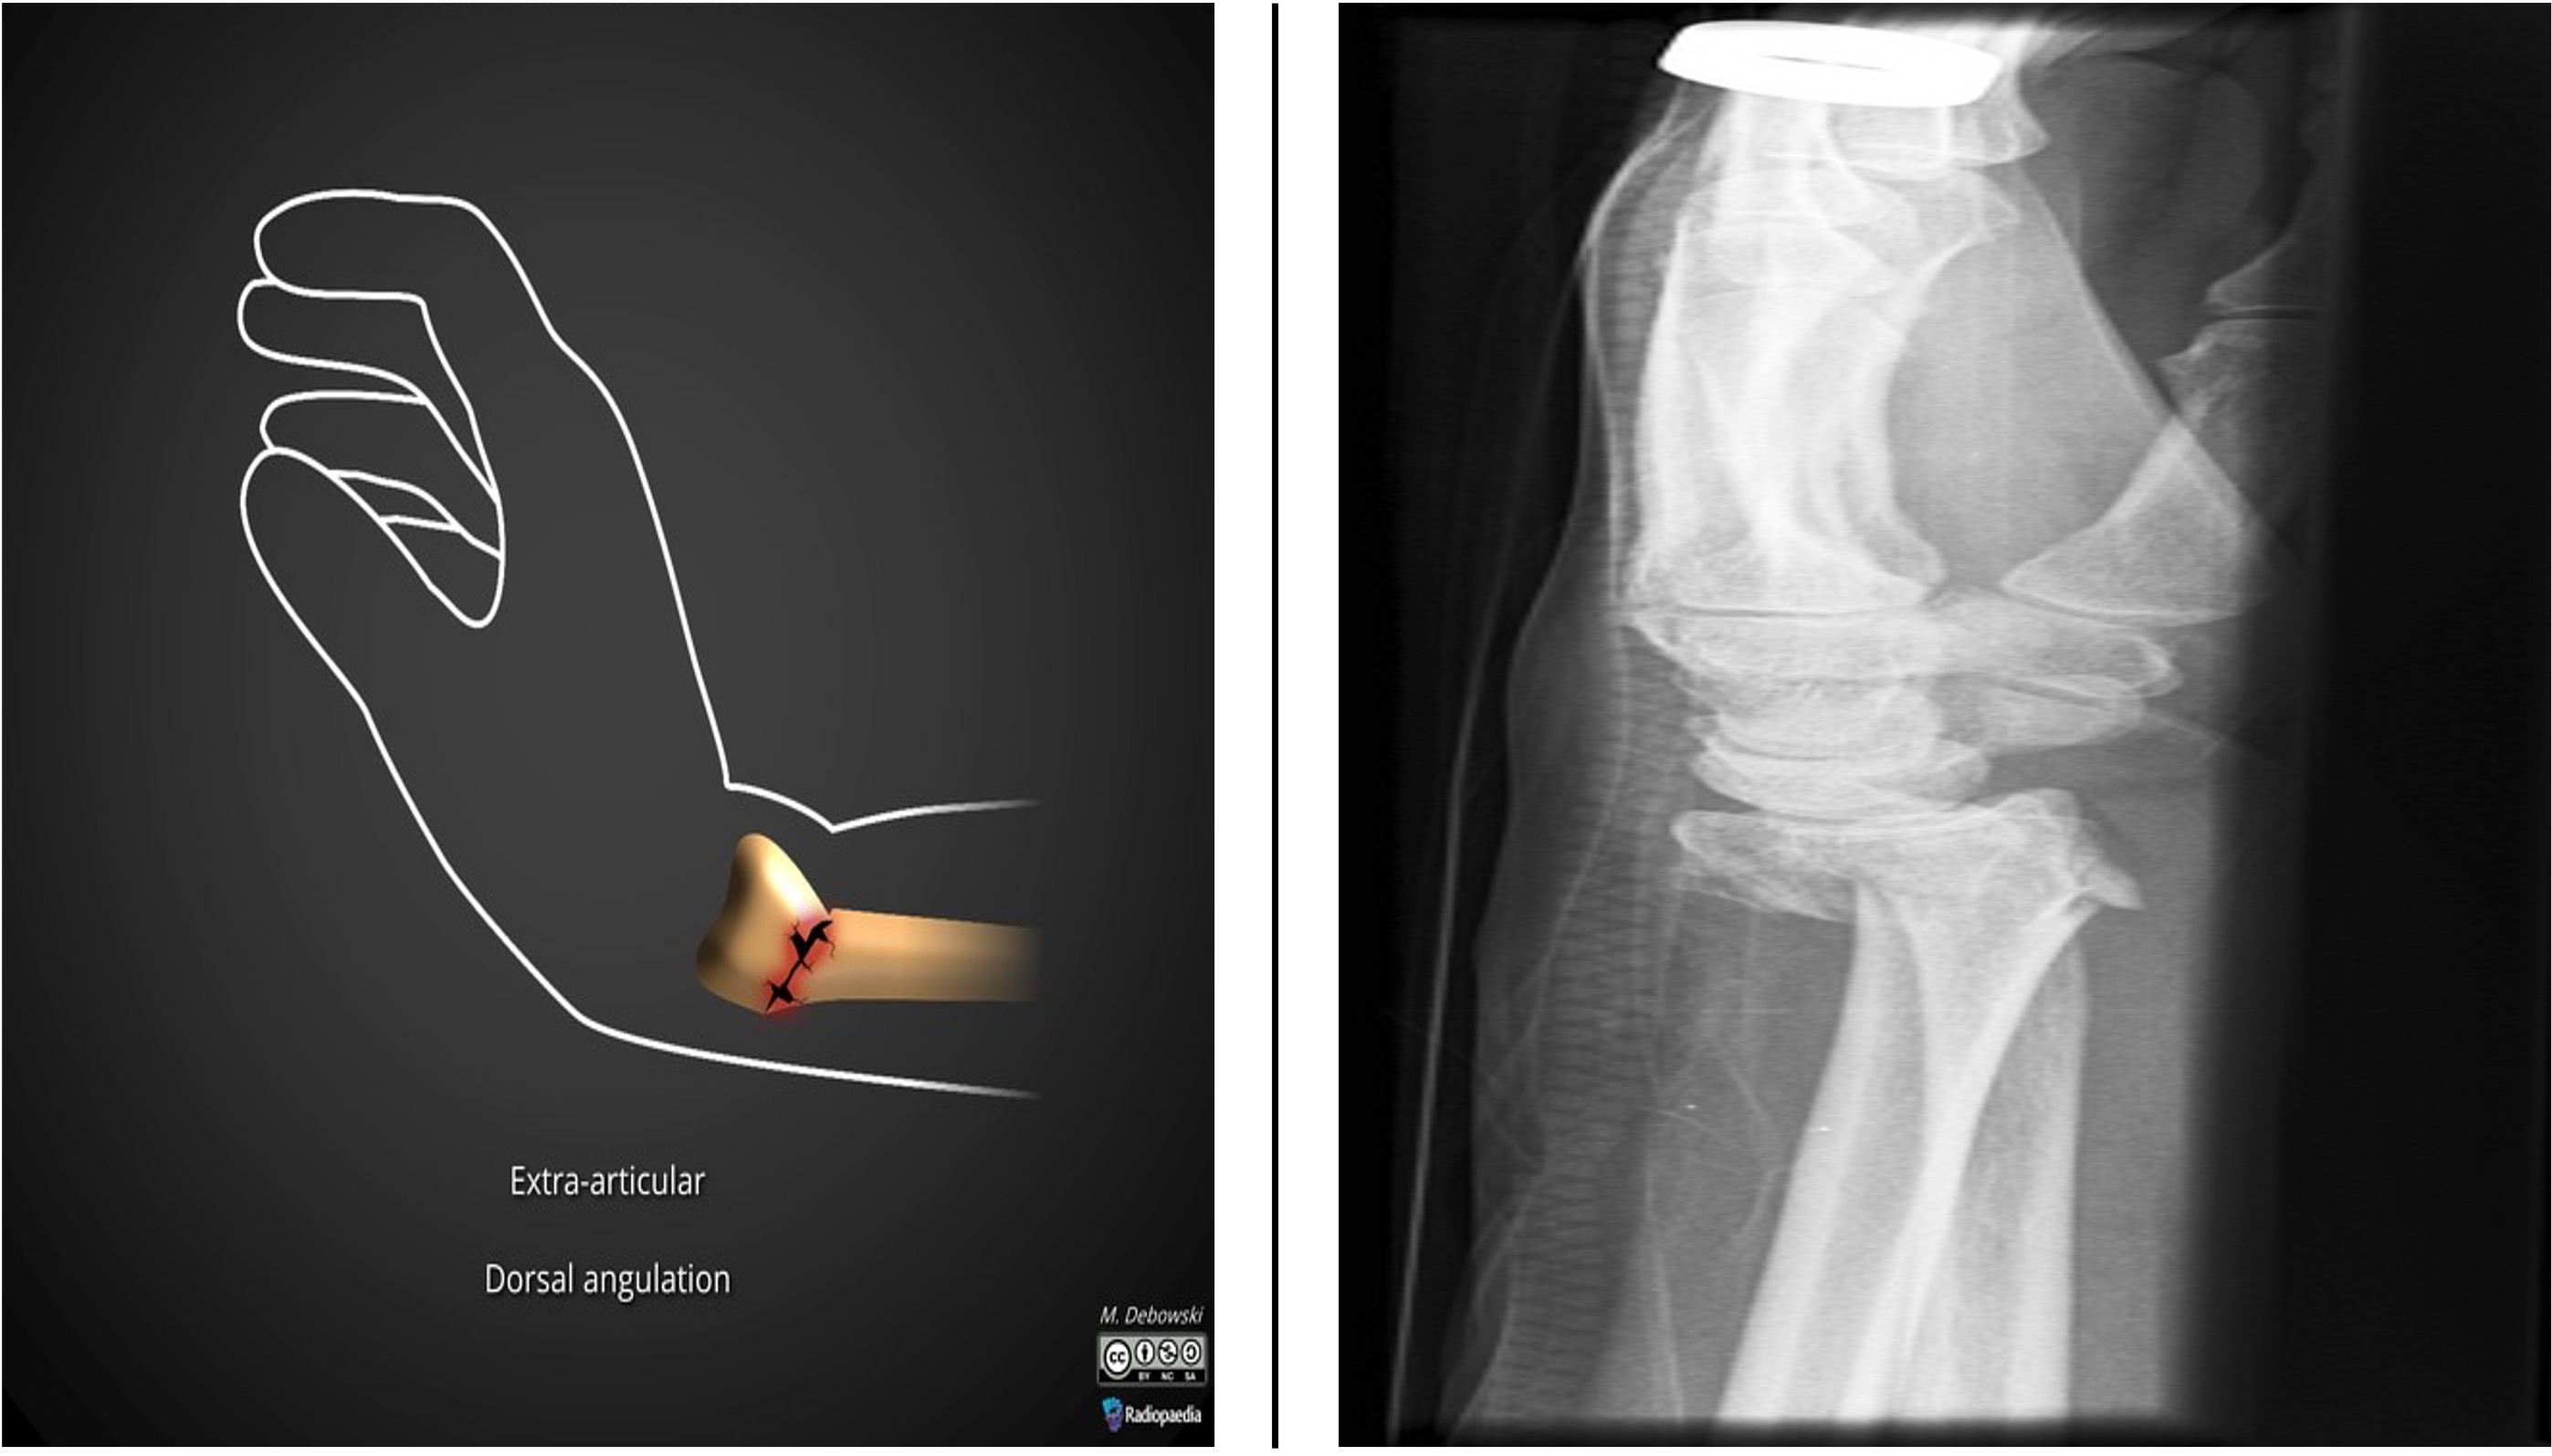

Diagnose

Fall på strak/suppinert arm. Vanlig fraktur hos voksne. Ofte lite klinikk. En klassisk sykehistorie: Fall på sykkel, lite smerte med en gang, til lege neste dag pga. økende smerte og redusert funksjon. Grensen mellom caput og collum går der knokkelen begynner å smalne av. Caputfrakturer er hyppigst hos voksne, collumfracturer sees oftest hos barn.

Røntgen

Albue - front utlagt og side + pronasjonsbilde. En fissur i caput eller collum er ofte vanskelig å se på røntgenbilde. Positivt fettputetegn er tegn på fraktur med blødning. Et rett sidebilde er en forutsetning for å vurdere om det er blod i leddet. Ved haemarthros vil man se et løftet seil på volarsiden (vanligst) og dorsalsiden av humerus i leddet. Dette skyldes at fettputen presses opp av blodet.

Behandling

De aller fleste frakturer skal behandles konservativt. Fallskade som beskrevet og væske i leddet behandles som fraktur. Ved fraktur med dislokasjon av caput radii bør operativ behandling vurderes hvis det er mekanisk hindret bevegelse i albuen. Et lite dislosert fragment kan fjernes. Et fragment som inkluderer mer enn 1/3 av leddflaten vurderes for fiksasjon. Collumfraktur med over 30 graders feilstilling eller 1/3 benbreddes dislokasjon bør vurderes operativt behandlet.

Konservativ behandling